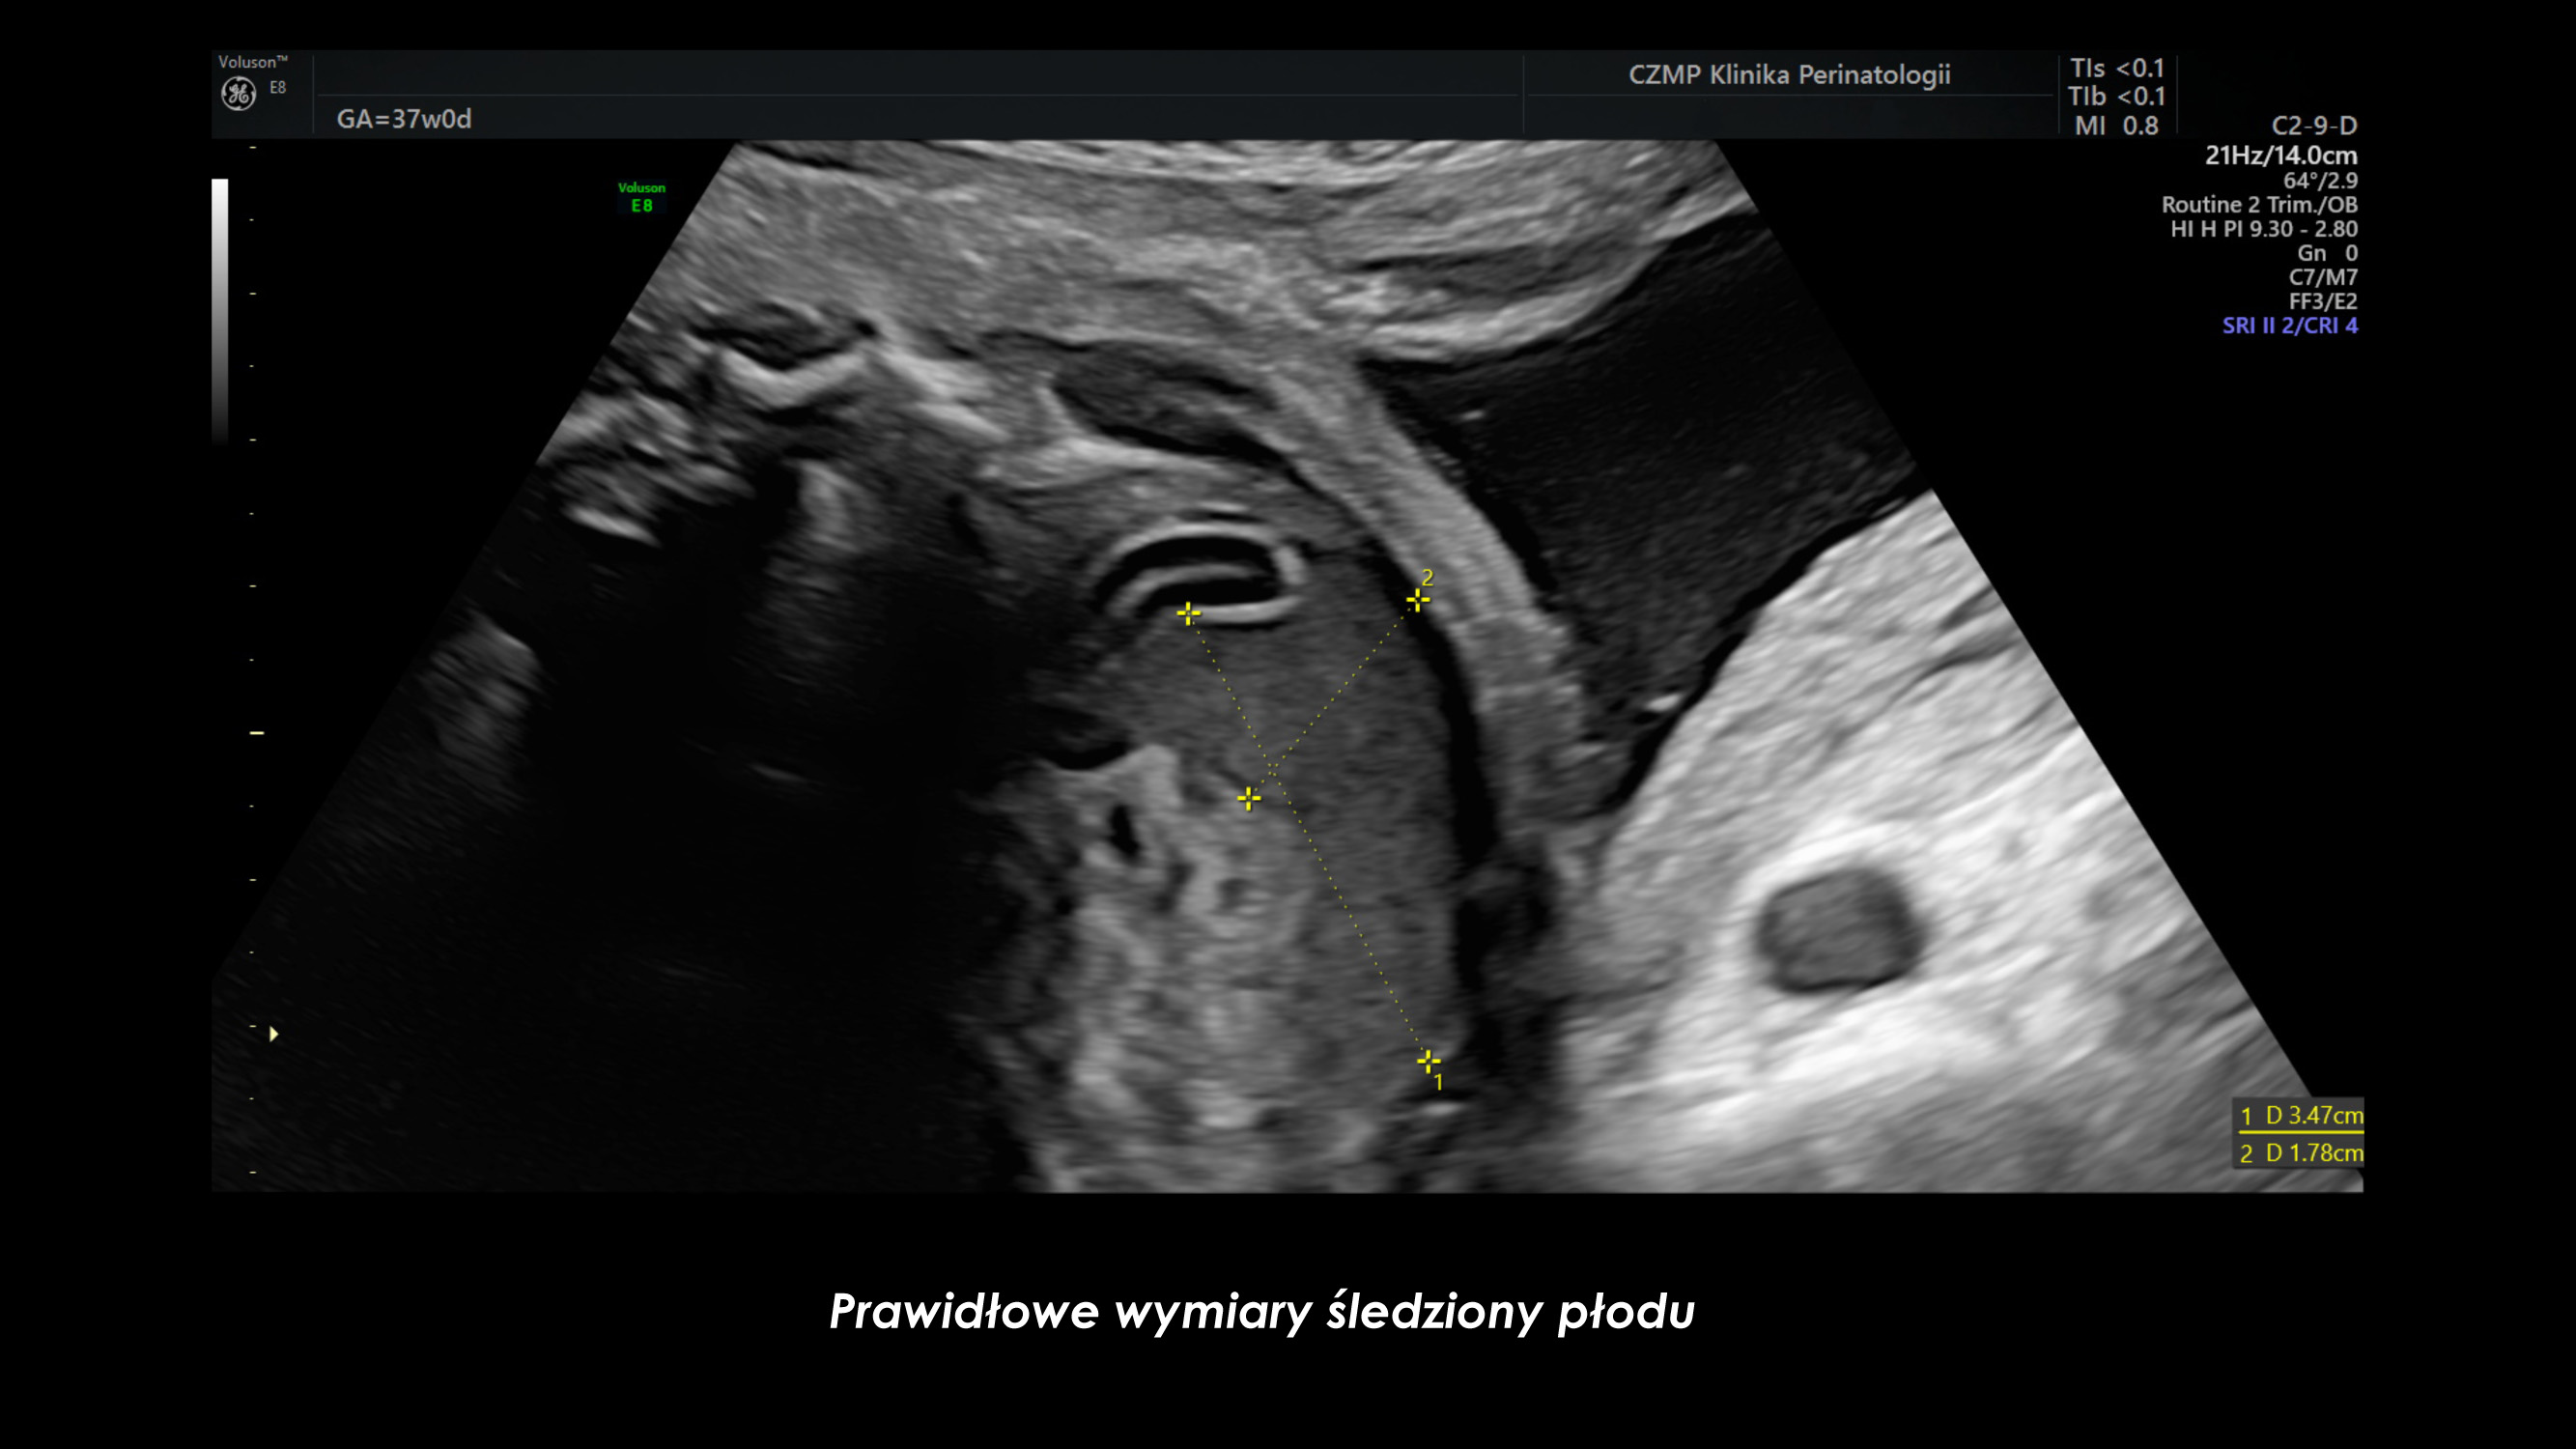

Nietypowy guz jamy brzusznej płodu